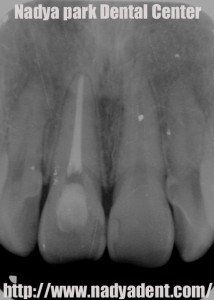

審美歯科 予防歯科 小児歯科 名古屋 症例

上の写真は根の治療の後のレントゲン写真です。

根の治療を終え、歯の神経が入っていたスペースに漂白の薬剤を置きます。

薬剤の交換を4回ほど行った(期間約1ヶ月)のちの写真が下の写真です。

矢印のついた歯が周囲の色に調和してきています